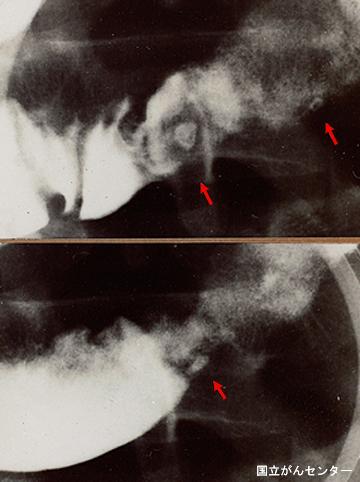

Ulcera de Intestino Delgado con el síndrome múltiple (supuesto síndrome de Churg - Strauss) que acompañan pirexia, tumor y heces sanguíneas

Tokyo Pref., Centro Nacional de curaciones de Cáncer, Hospital Central y Centro Kyusyu de Curaciones de Cáncerc

Enfermedad Inflamatoria - Ulcerativa/otros

intestino delgado/ileón

Rayos X

1 - 9